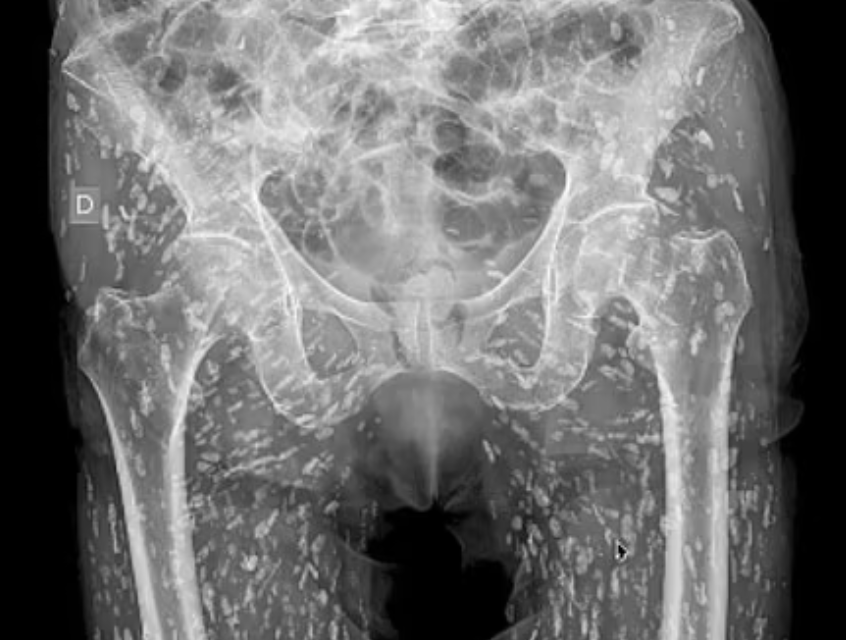

أظهرت صور أشعة سينية مرعبة جسد رجل مليئًا ببيض الدودة الشريطية بعد خطأ حيوي في المطبخ أدى إلى غزو طفيلي.

وبمجرد تناولها، تشكل الديدان الشريطية أكياسًا متكلسة صلبة أو بيضًا ميتًا “زومبيًا” يمكن أن تشعر وكأنها كتل تحت الجلد، وتظهر مثل “حبة الأرز” في الفحوصات الطبية.

وفي الصورة التي شاركها الدكتور غالي، يمكن رؤية حوض رجل مرقط بمئات من هذه الأكياس المتكلسة.